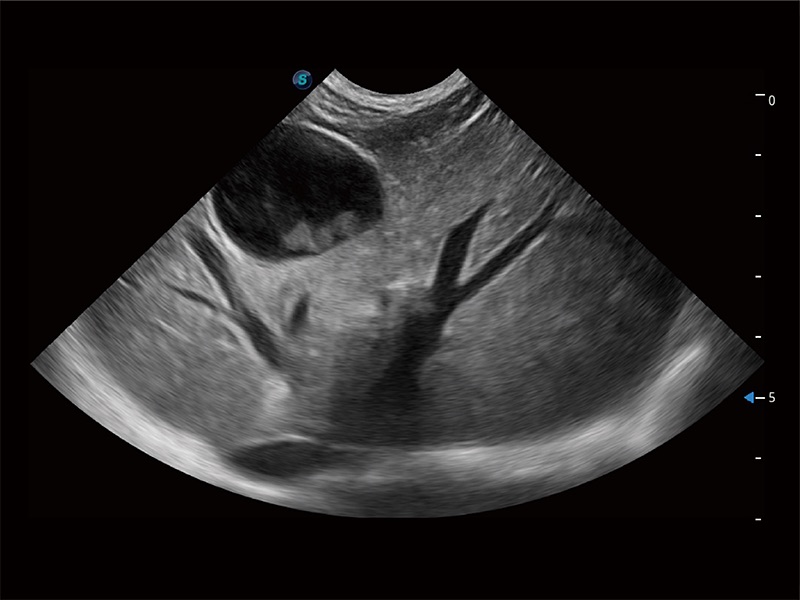

(犬)肠道